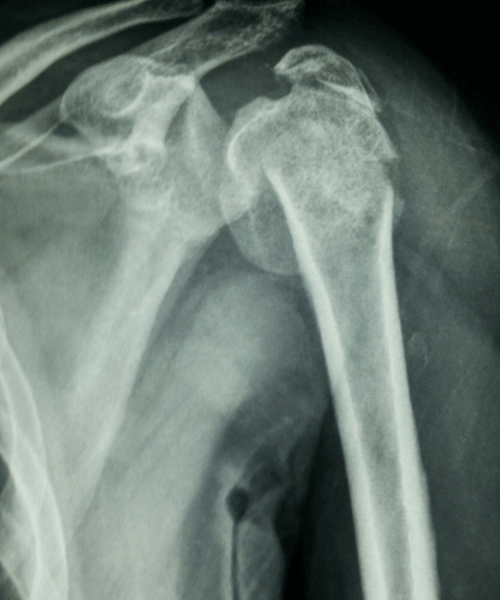

Case:21 Closed fracture of the neck of humerus with dislocation of Right shoulder

A female patient, aged 82 years had been diagnosed to have Closed fracture of the neck of humerus with dislocation of Right shoulder. She was treated operatively with Reduction & Internal fixation.

Pre-Operative

Post-Operative Ap View

Post-Operative Lateral View